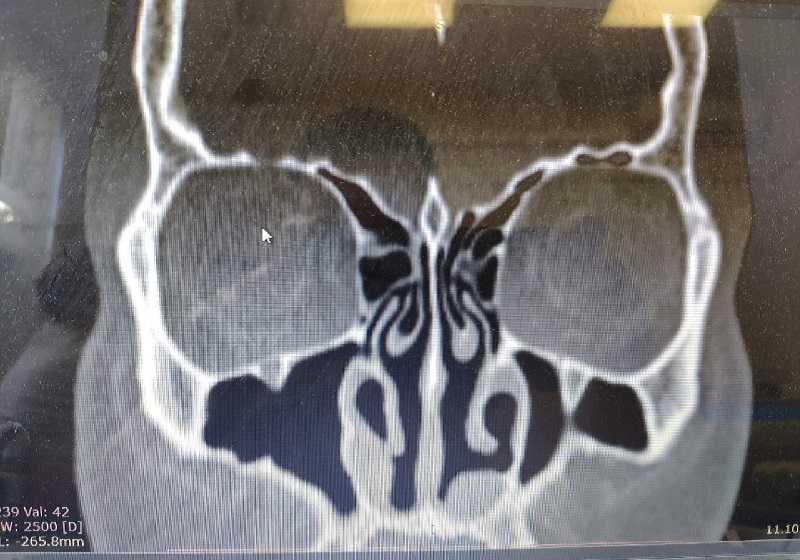

На данном скане видны довольно большие трансплантаты из ребра диаметром почти в 1 см. Ранее пациентке провели почти полное удаление раковин испанские хирурги. Длительное время ее беспокоили в основном обильные выделения. После проведенной мною трансплантации ребра под общей анестезией, выделения практически исчезли, пациентка начала жить обычной жизнью.